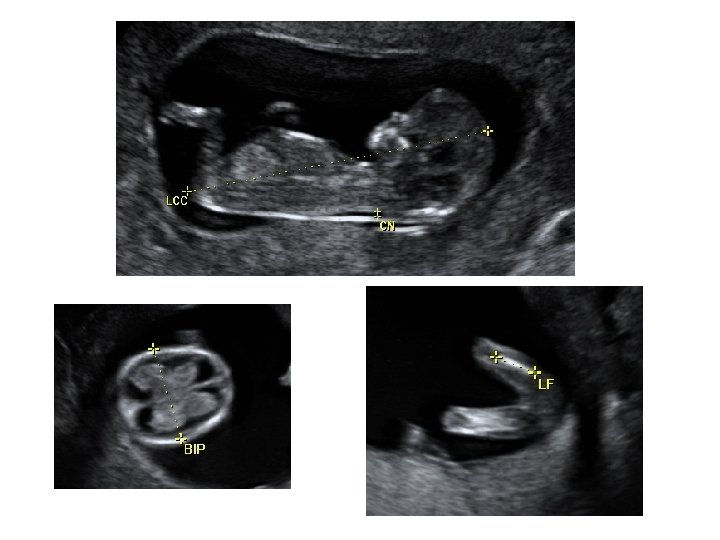

Échographie du 1 er trimestre • Entre 11 et 14 SA • Étudier la vitalité de l’embryon • Dater le début de la grossesse - LCC : longueur cranio-caudale - BIP : diamètre bipariétal - DAT : diamètre abdominale transverse - LF : longueur fémorale Ces mesures, à ce terme de la grossesse, donnent le terme avec une précision de ± 5 jours

Échographie du 2ème trimestre • Entre 21 et 23 SA • Évaluer la croissance fœtale - pôle céphalique BIP : diamètre bipariétal PC : périmètre céphalique - abdomen fœtal CA : circonférence abdominale - extrémités : LF : longueur fémorale